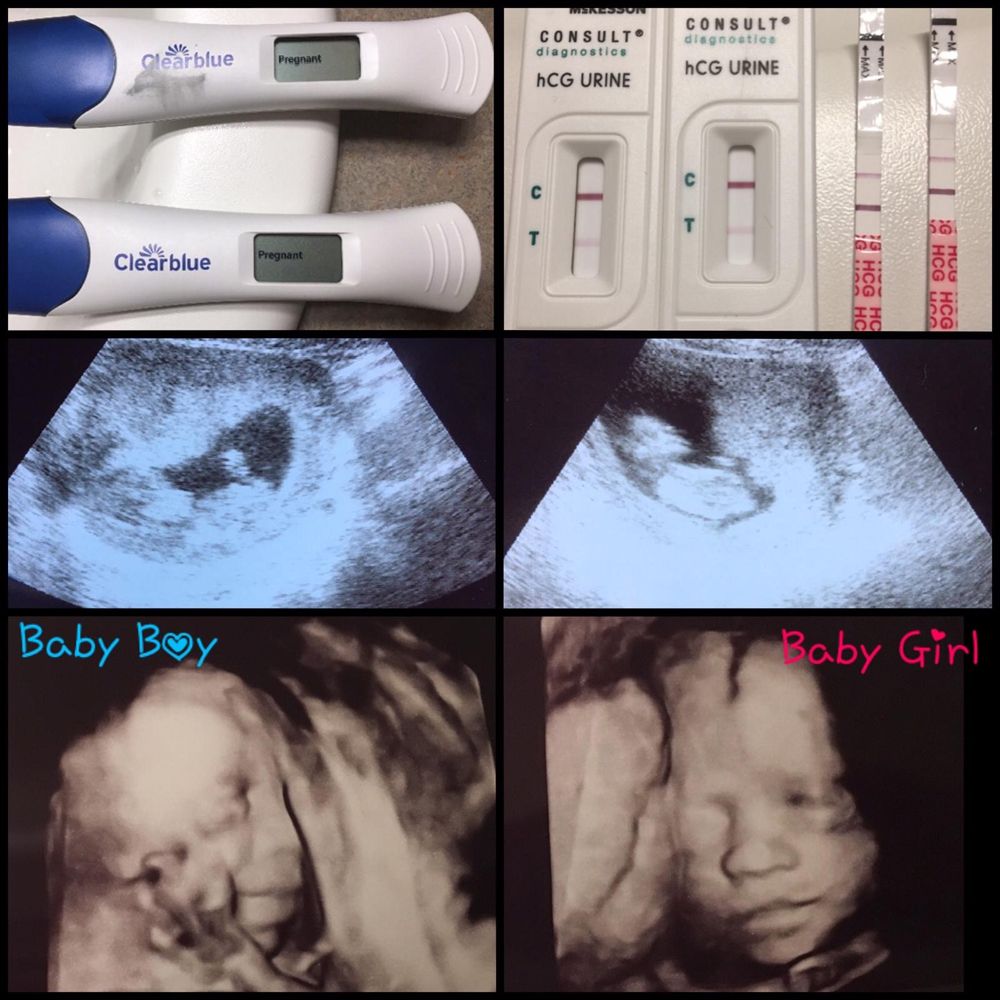

“Days later, in our tiny new apartment in Los Angeles, we got a test for Kelly to take. Two lines appeared, but they were so faint that we didn't know what they meant."

“I said to her, 'My blood test has shown I'm not pregnant, so why don't I take a test, too, as a control?'"

She continued:

“But when I did, mine looked the same – two little lines."

For clarification, Kelly and Karina sent a photo of the tests to a nurse friend – who replied saying she thought they were both pregnant.

Karina added:

“We took some more tests which confirmed it. We were both expecting, and around four weeks along."